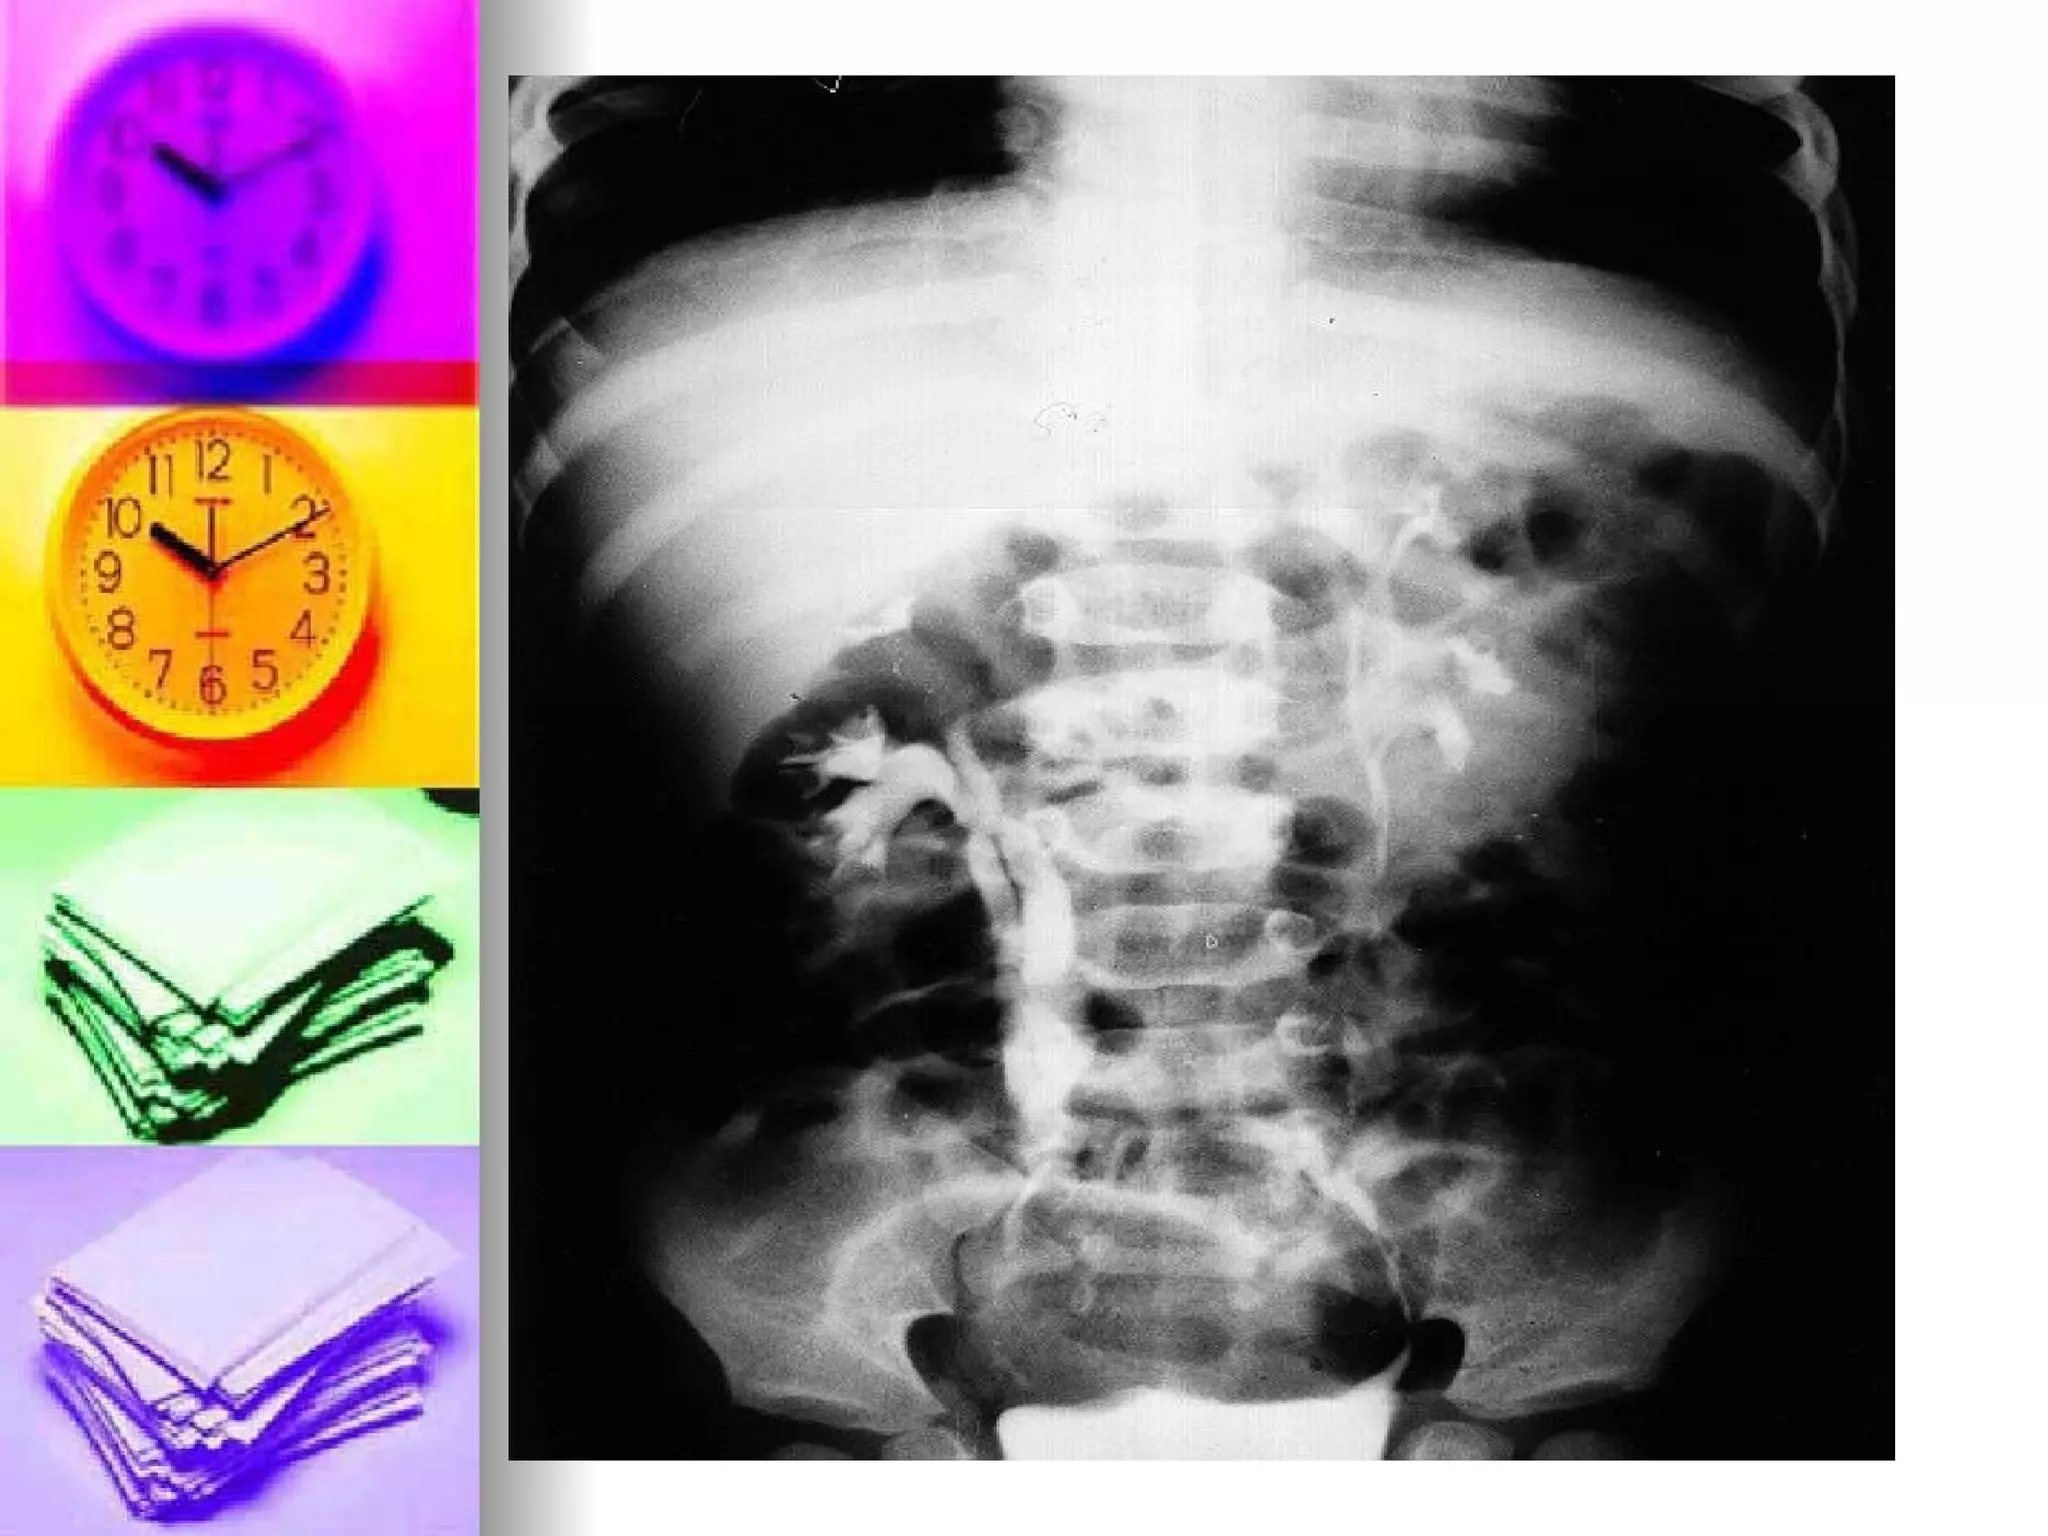

GIT Visualization Barium Enema- LGIS Pretest: Informed consent, NPO the night, Enema the morning Intratest: Position on  LEFT side, administer enema, then X-ray follow Post-test: Cleansing enema , Laxative for constipation, assess for intestinal obstruction

GIT Visualization BariumEnema- LGIS Pretest: Informed consent, NPO the night, Enema the morning Intratest: Position on LEFT side, administer enema, then X-ray follow Post-test: Cleansing enema , Laxative for constipation, assess for intestinal obstruction